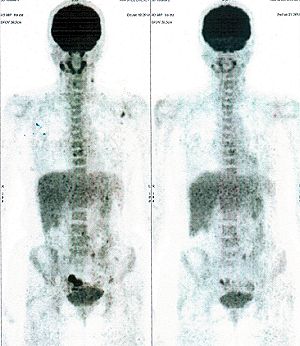

CASE NO: 3 (PROSTATE CANCER)

A middle-aged man with castration resistant prostate cancer, having failed all currently available cancer treatment, was very weak, and getting worse every day. The PET/CT scan showed he had massive bone metastases. After a few treatment, all the bone metastases went into remission. About 6 months later, he is still in remission.